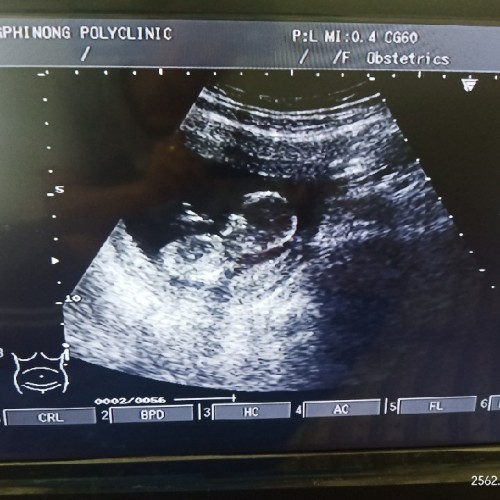

ขอสอบถามหน่อยค่ะ อายุครรภ์ 14 w4d เด็กในท้องขนาดนี้ไหมค่ะ ท้องแรกค่ะ พอดีลองเทียบกับคนข้างๆคือในใบซาวอายุครรภ์ใกล้ๆกัน ของเขาเป็นรูปร่างเด็กแล้วคะ กังวลจังเลยคะ

ของเราตอน14week

ของเรา14w1d ค่า